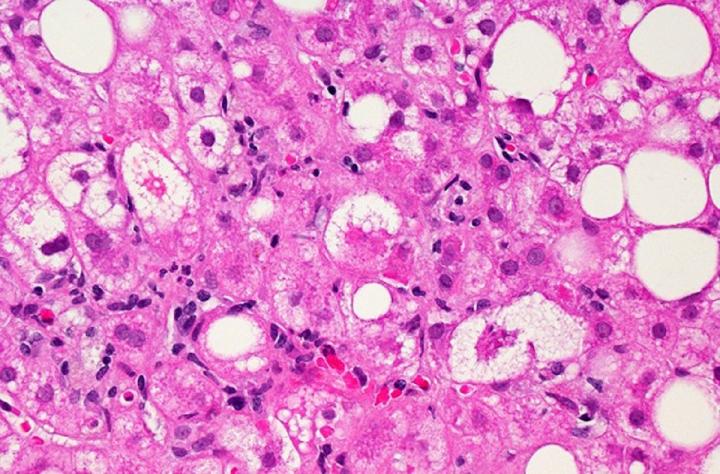

Non-alcoholic fatty liver disease, or NAFLD, frequently occurs alongside HIV, affecting as many as 25% of people living with HIV in the developed world. However, no effective treatments currently exist to treat the condition, which is a risk factor for progressive liver disease and liver cancer. Investigators led by Colleen M. Hadigan, M.D., senior research physician in NIAID's Laboratory of Immunoregulation, and Steven K. Grinspoon, M.D., Chief of the Metabolism Unit at MGH, tested whether tesamorelin could decrease liver fat in men and women living with both HIV and NAFLD. Among the participants enrolled, 43% had at least mild fibrosis, and 33% met the diagnostic criteria for a more severe subset of NAFLD called nonalcoholic steatohepatitis (NASH). Thirty-one participants were randomized to receive daily 2-mg injections of tesamorelin, and 30 were randomized to receive identical-looking injections containing a placebo. Researchers provided nutritional counseling to all participants, as well as training in self-administering the daily injections. Researchers then compared measures of liver health in both groups at baseline and 12 months.

After one year, participants receiving tesamorelin had better liver health than those receiving placebo, as defined by reduction in hepatic fat fraction (HFF)--the ratio of fat to other tissue in the liver. The healthy range for HFF is less than 5%. Thirty-five percent of study participants receiving tesamorelin achieved a normal HFF, while only 4% of those on placebo reached that range with nutritional advice alone. Overall, tesamorelin was well-tolerated and reduced participants' HFF by an absolute difference of 4.1% (corresponding to a 37% relative reduction from the beginning of the study). While nine participants receiving placebo experienced onset or worsening of fibrosis, only two participants in the tesamorelin group experienced the same. Additionally, levels of several blood markers associated with inflammation and liver damage--including the enzyme alanine aminotransferase (ALT)--decreased more among those taking tesamorelin compared to those on a placebo, particularly among those with increased levels at the beginning of the study.

While liver disease is often associated with heavy alcohol use, NAFLD occurs when excess fat builds up in the liver without alcohol as a contributing factor. This condition may progress to liver damage, cirrhosis or cancer that could be life-threatening and necessitate liver transplantation.